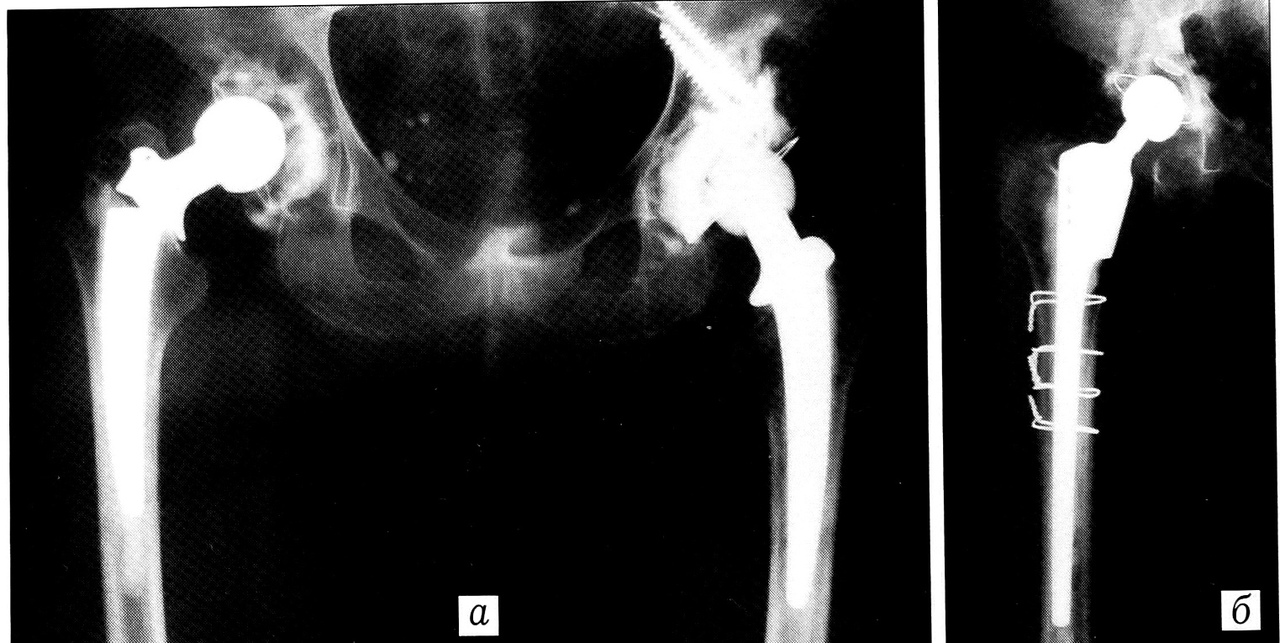

Особенности замены эндопротеза Сиваша. Выполняя ревизионное вмешательство, мы использовали прежний кожный доступ. При обнажении вертельно-подвертельной области бедренной кости обращали внимание на состояние вертела в зоне шпонки конструкции: в половине случаев вокруг нее имелся большой дефект костной ткани и определялась подвижность вертела, который сохранял связь с бедренной костью только за счет рубца (рис. 2). В этих случаях вертел отсекали, экономно удаляли некротические ткани и открывали доступ к тазовому компоненту протеза. Шпонку удаляли не всегда, иногда она помогала при выбивании ножки эндопротеза. При хорошем состоянии большого вертела шпонку удаляли с минимальной травматизацией костной ткани, затем открывали область тазобедренного сустава по принципу доступа Хардинга — без отсечения большого вертела. Это имеет важное значение для предупреждения в дальнейшем вывиха реэндопротеза.

Рис. 2. Рентгенограммы больной 62 лет. а — нестабильность эндопротеза (Сиваша) левого тазобедренного сустава; б — состояние после ревизионного тотального эндопротезирования цементируемым протезом ЭСИ.